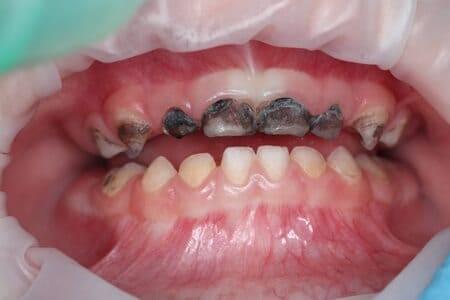

Детальніше...У Центрі Дитячої Стоматології лікаря Ковнацького ми віримо, що візит до стоматолога має бути для дитини не приводом для страху, а кроком до здорової та щасливої посмішки. Наша філософія базується на глибокому розумінні дитячої психології та фізіології, адже дитячі зуби потребують особливого підходу, а малюки – щирої турботи та довіри.